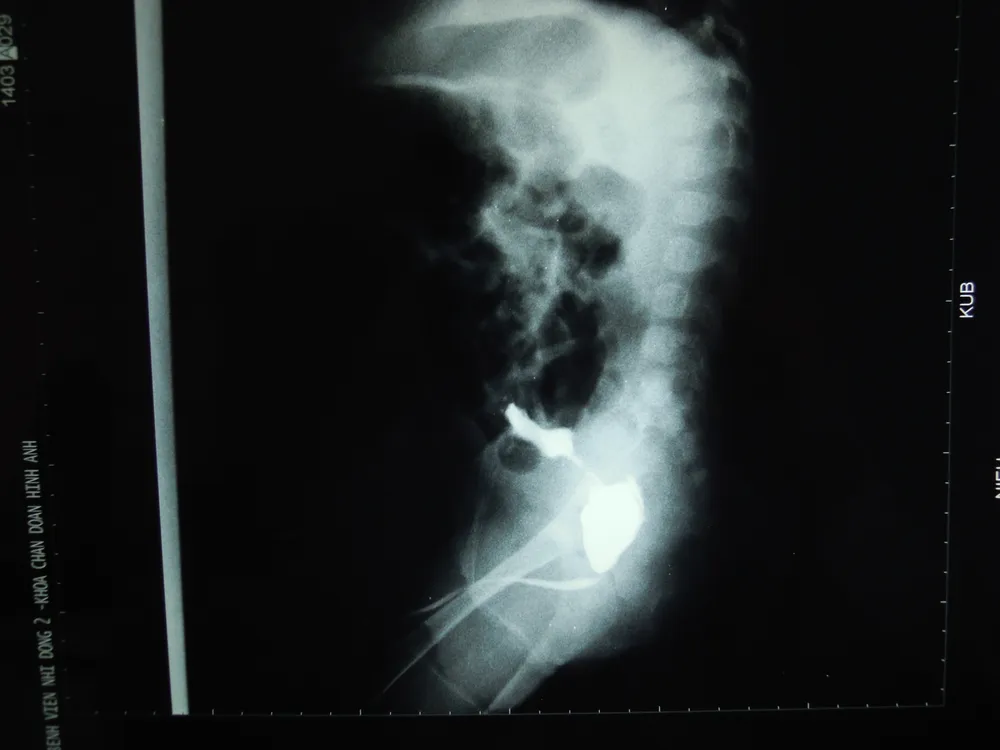

Bé nhập viện trong tình trạng bứt rứt, suy thận cấp. Kết quả thăm khám lâm sàng và hình ảnh chụp phim x-quang cho thấy bàng quang đã bị vỡ, bờ nham nhở. Siêu âm phát hiện ra hai niệu quản giãn, thận ứ nước 2 bên và nước tiểu tràn ngập trong ổ bụng. Hình ảnh niệu đạo cản quang cho thấy van niệu đạo sau là nguyên nhân chính.

Hình ảnh Cận lâm sàng thành bàng quang nham nhở